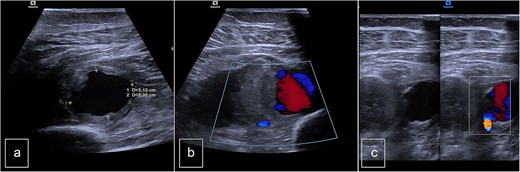

The Doppler ultrasonography was supplemented with contrast-enhanced computed tomography (CT angiography) and 3D reconstructions. The CT scan identified a hematoma with a pseudoaneurysm located at the inferior aspect, measuring 28 mm in height, 29 mm in the transverse axis, and 20 mm in the anteroposterior axis. The lesion was supplied by the PTA, which flowed laterally to the pseudoaneurysm. The medial wall of the PTA appeared discontinuous over a length of ~6 mm (Fig. 2).

Computed tomography. (a) Lateral view, (b) posterior view, and (c) vascular reconstruction. The medial wall of the posterior tibial artery appeared discontinuous over a length of ~6 mm.